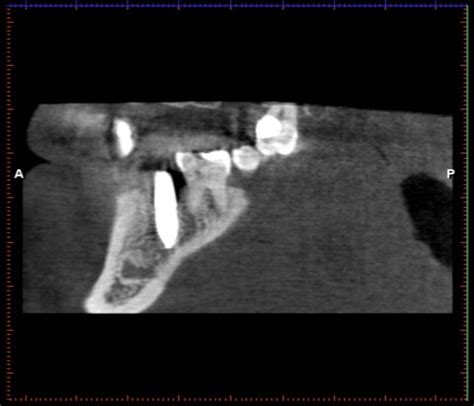

La radiografía periapical es una herramienta diagnóstica fundamental, pero presenta limitaciones en la detección de lesiones apicales en comparación con la tomografía computarizada de haz cónico (CBCT). El CBCT ofrece una mayor precisión en la visualización de las estructuras anatómicas y la detección de lesiones periapicales, lo que puede ser especialmente útil en casos complejos o cuando la radiografía periapical no proporciona suficiente información.

Examen Clínico y Radiográfico: En 2022, la paciente no presentaba síntomas, pero se observó un aumento de la lesión radiolúcida periapical (PAI 4). El estudio mediante CBCT reveló una afectación conjunta de los tejidos periapicales en los dientes 2.1 y 2.2, así como la perforación de las tablas óseas palatina y vestibular.

Seguimiento: Se realizó el seguimiento con radiografías periapicales y, a los 20 meses, se realizó un control con CBCT de campo limitado para verificar la evolución de las tablas óseas y las características de la lesión.